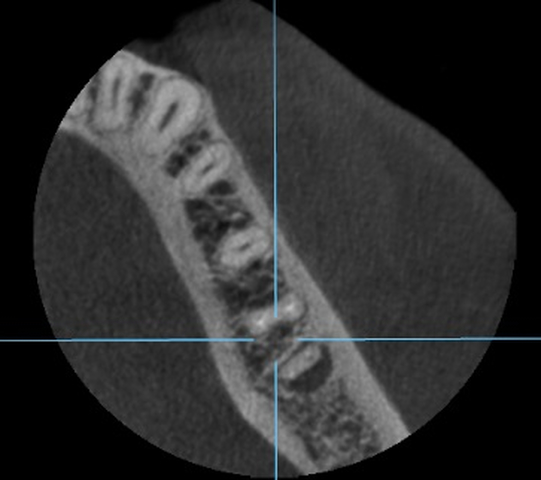

Diagnostykę poszerzono o badanie tomografii wiązki stożkowej (ryc. 4-6). Region implantacji zwymiarowano w trzech płaszczyznach w specjalnym programie komputerowym 3Shape Implant Studio® (3Shape, Kopenhaga, Dania), wykonano szablon implantologiczny i przystąpiono do procedury chirurgicznej. Zaprojektowano użycie wszczepu o wymiarach 4,2 x 10 mm.

Ryc. 4. Przekrój zęba 36 w płaszczyźnie czołowej. Ryc. 5. Przekrój zęba 36 w płaszczyźnie strzałkowej.

Ryc. 6. Przekrój zęba 36 w płaszczyźnie horyzontalnej.